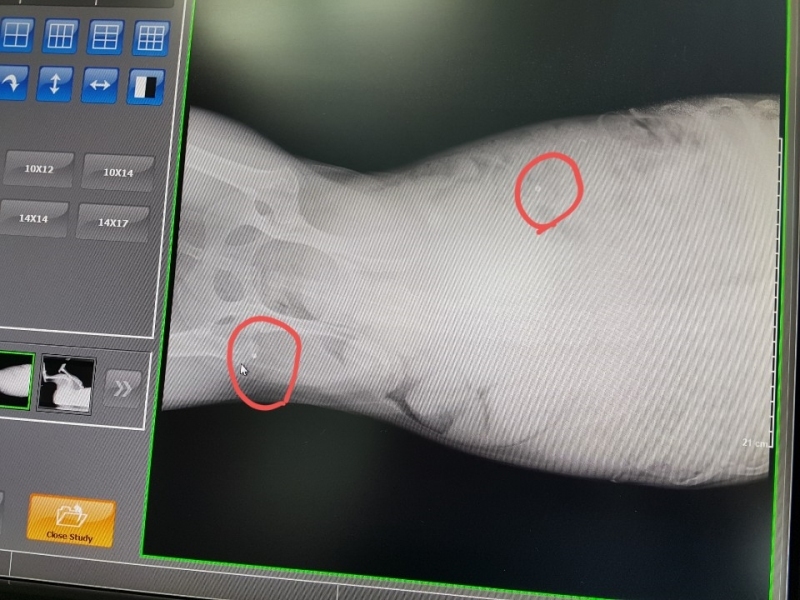

¿À´Ã ¼º³²¿¡ Àִ µ¿¹°º´¿ø¿¡ °¡¼­ ¿¢½º·¹À̸¦ Âï¾îº» °á°ú

½ÇźÀÌ ¿©·¯¹ß ¹ÚÇôÀִµ¥  ¼ö¼úÀ» ¸øÇÏ°í ¸Ô´Â°ÍÀº Àß ¸ÔÀ¸´Ï

°ßÀÌ ¸Ô´Â°Íµµ À߸԰í Ȱ¹ßÇѵ¥  ¿ÞÂÊ ¹ß¸ñÀ» ¾²Áö ¸øÇÕ´Ï´Ù,

¿ÞÂÊ´Ù¸® ¹ß¸ñ¿¡ ½ÇźÀÌ ¹ÚÇôÀִµ¥ »À¸¦ ¸Â°í ½ÇźÀÌ ºÎ¼­Áø ´À³¦ÀÔ´Ï´Ù,

2¿ù 15ÀÏ ±¤Áֽà ÃÊ¿ù¸é¿¡ ÀÖ´Â À̼ٵ¿¹° º´¿ø¿¡¼­ Á¤¹Ð ¿¢½º·¹ÀÌ ÃÔ¿µ ÇßÀ¾´Ï´Ù,

´Ù¸®¿¡ ºÎ¼­Áø ¿±ÅºÀº »À¿¡ ¸Â¾Æ »À°¡ ±ÝÀ̰¡°í ¾à°£Àº »À¼ÓÀ¸·Î µé¾î °¬´Âµ¥

ºÎ¼­Áø ¿±ÅºÀ» »©´Â ¼ö¼úÀº ºÒ°¡´ÉÇÏ°í µ¿¹°Àº »ç¶÷ÇÏ°í ´Þ¸® ÀÌ»óÇÑ ¹°Ã¼°¡ µé¾î¿À¸é

Ç×ü°¡ »ý°Ü¼­ ¹°Ã¼¸¦ ¿¡¿ö½×°í ¸·ÀÌ »ý°Ü  ´õ´Â ÀÌ»óÀÌ ¾ø°í »ç´Âµ¥´Â ÁöÀåÀÌ ¾ø´Ù°í ÇϽôõ±º¿ä.

¿±ÅºÀÌ ½ÉÀå, Æó, ³»Àå±îÁö µé¾î°¡¸é À§ÇèÇѵ¥ ¸ö¼Ó¿¡ ¹ÛÈù°ÍÀº

¸Ô±â¸¸ ÀßÇÏ¸é »ì¼ö ÀÖ°í 3ÁÖ ÈÄ¿£ °ÅÀÇ Á¤»ó±îÁö ¿À´Ï±î ½Ã°£À» °¡Áö°í

±â´Ù·Á º¸¶ó´Â  µ¿¹°º´¿ø¿øÀå´ÔÀÇ Á¾ÇÕÀûÀÎ ÆÇ´ÜÀÔ´Ï´Ù,